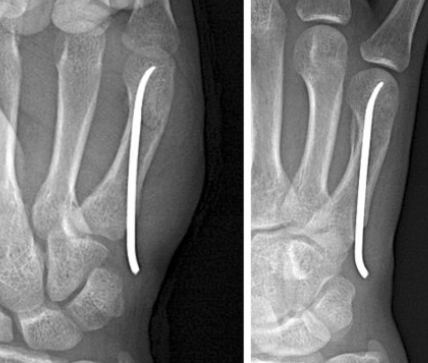

골절 부위가 많이 꺾이거나 뼈의 위치가 맞지 않아 비수술적 방법으로는 도저히 정복이 어려운 경우, 수술을 하여 핀 삽입이나 나사 혹은 금속판 고정을 통해 뼈를 고정합니다.

골절 상태에 따라 핀고정(K강선)이나 나사 고정술을 시행합니다.